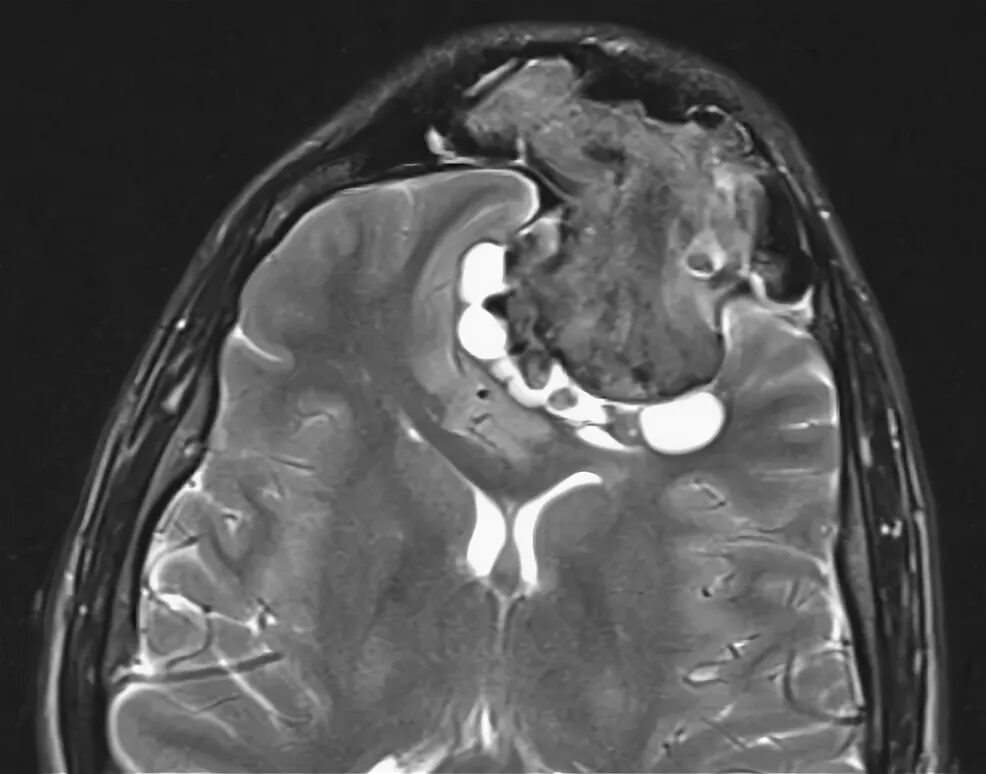

Остеома мрт